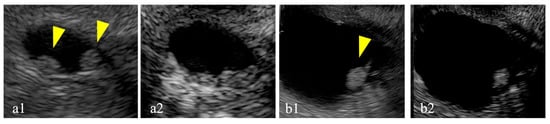

Of the 68 cases, 17 with enhancing MNs larger than 5 mm on CE-EUS were classified as having high-risk stigmata. Among these, DFI-EUS identified linear or dotted signals within the MNs in 14 (82%) cases. Surgery was performed for 13 of these 17 cases (Figure 5). The final pathological diagnosis of the surgically resected cases included low-grade dysplasia for six cases and intraductal papillary mucinous carcinoma for seven cases. Among the seven intraductal papillary mucinous carcinoma cases, DFI-EUS detected dotted signals in two cases and linear signals in four cases; one case was difficult to evaluate. Similarly, among the six low-grade dysplasia cases, dotted signals were observed in two cases and linear signals were observed in three cases; one case was difficult to evaluate. No significant association between the pathological diagnosis and DFI signal findings was observed (p = 1.00).

Figure 5. Detective flow imaging of mural nodules in surgically resected cases. Linear vessels are observed inside the mural nodule, intraductal papillary mucinous carcinoma (a,b), and low-grade dysplasia (c).